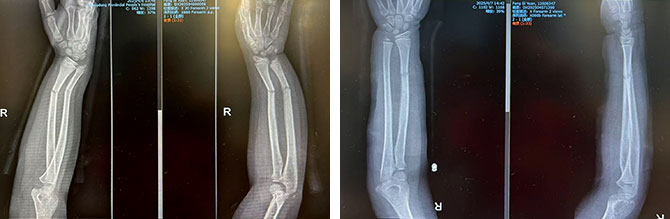

患者1:女,8岁,右侧桡尺骨双骨折,复位前后对比

复位前 复位后